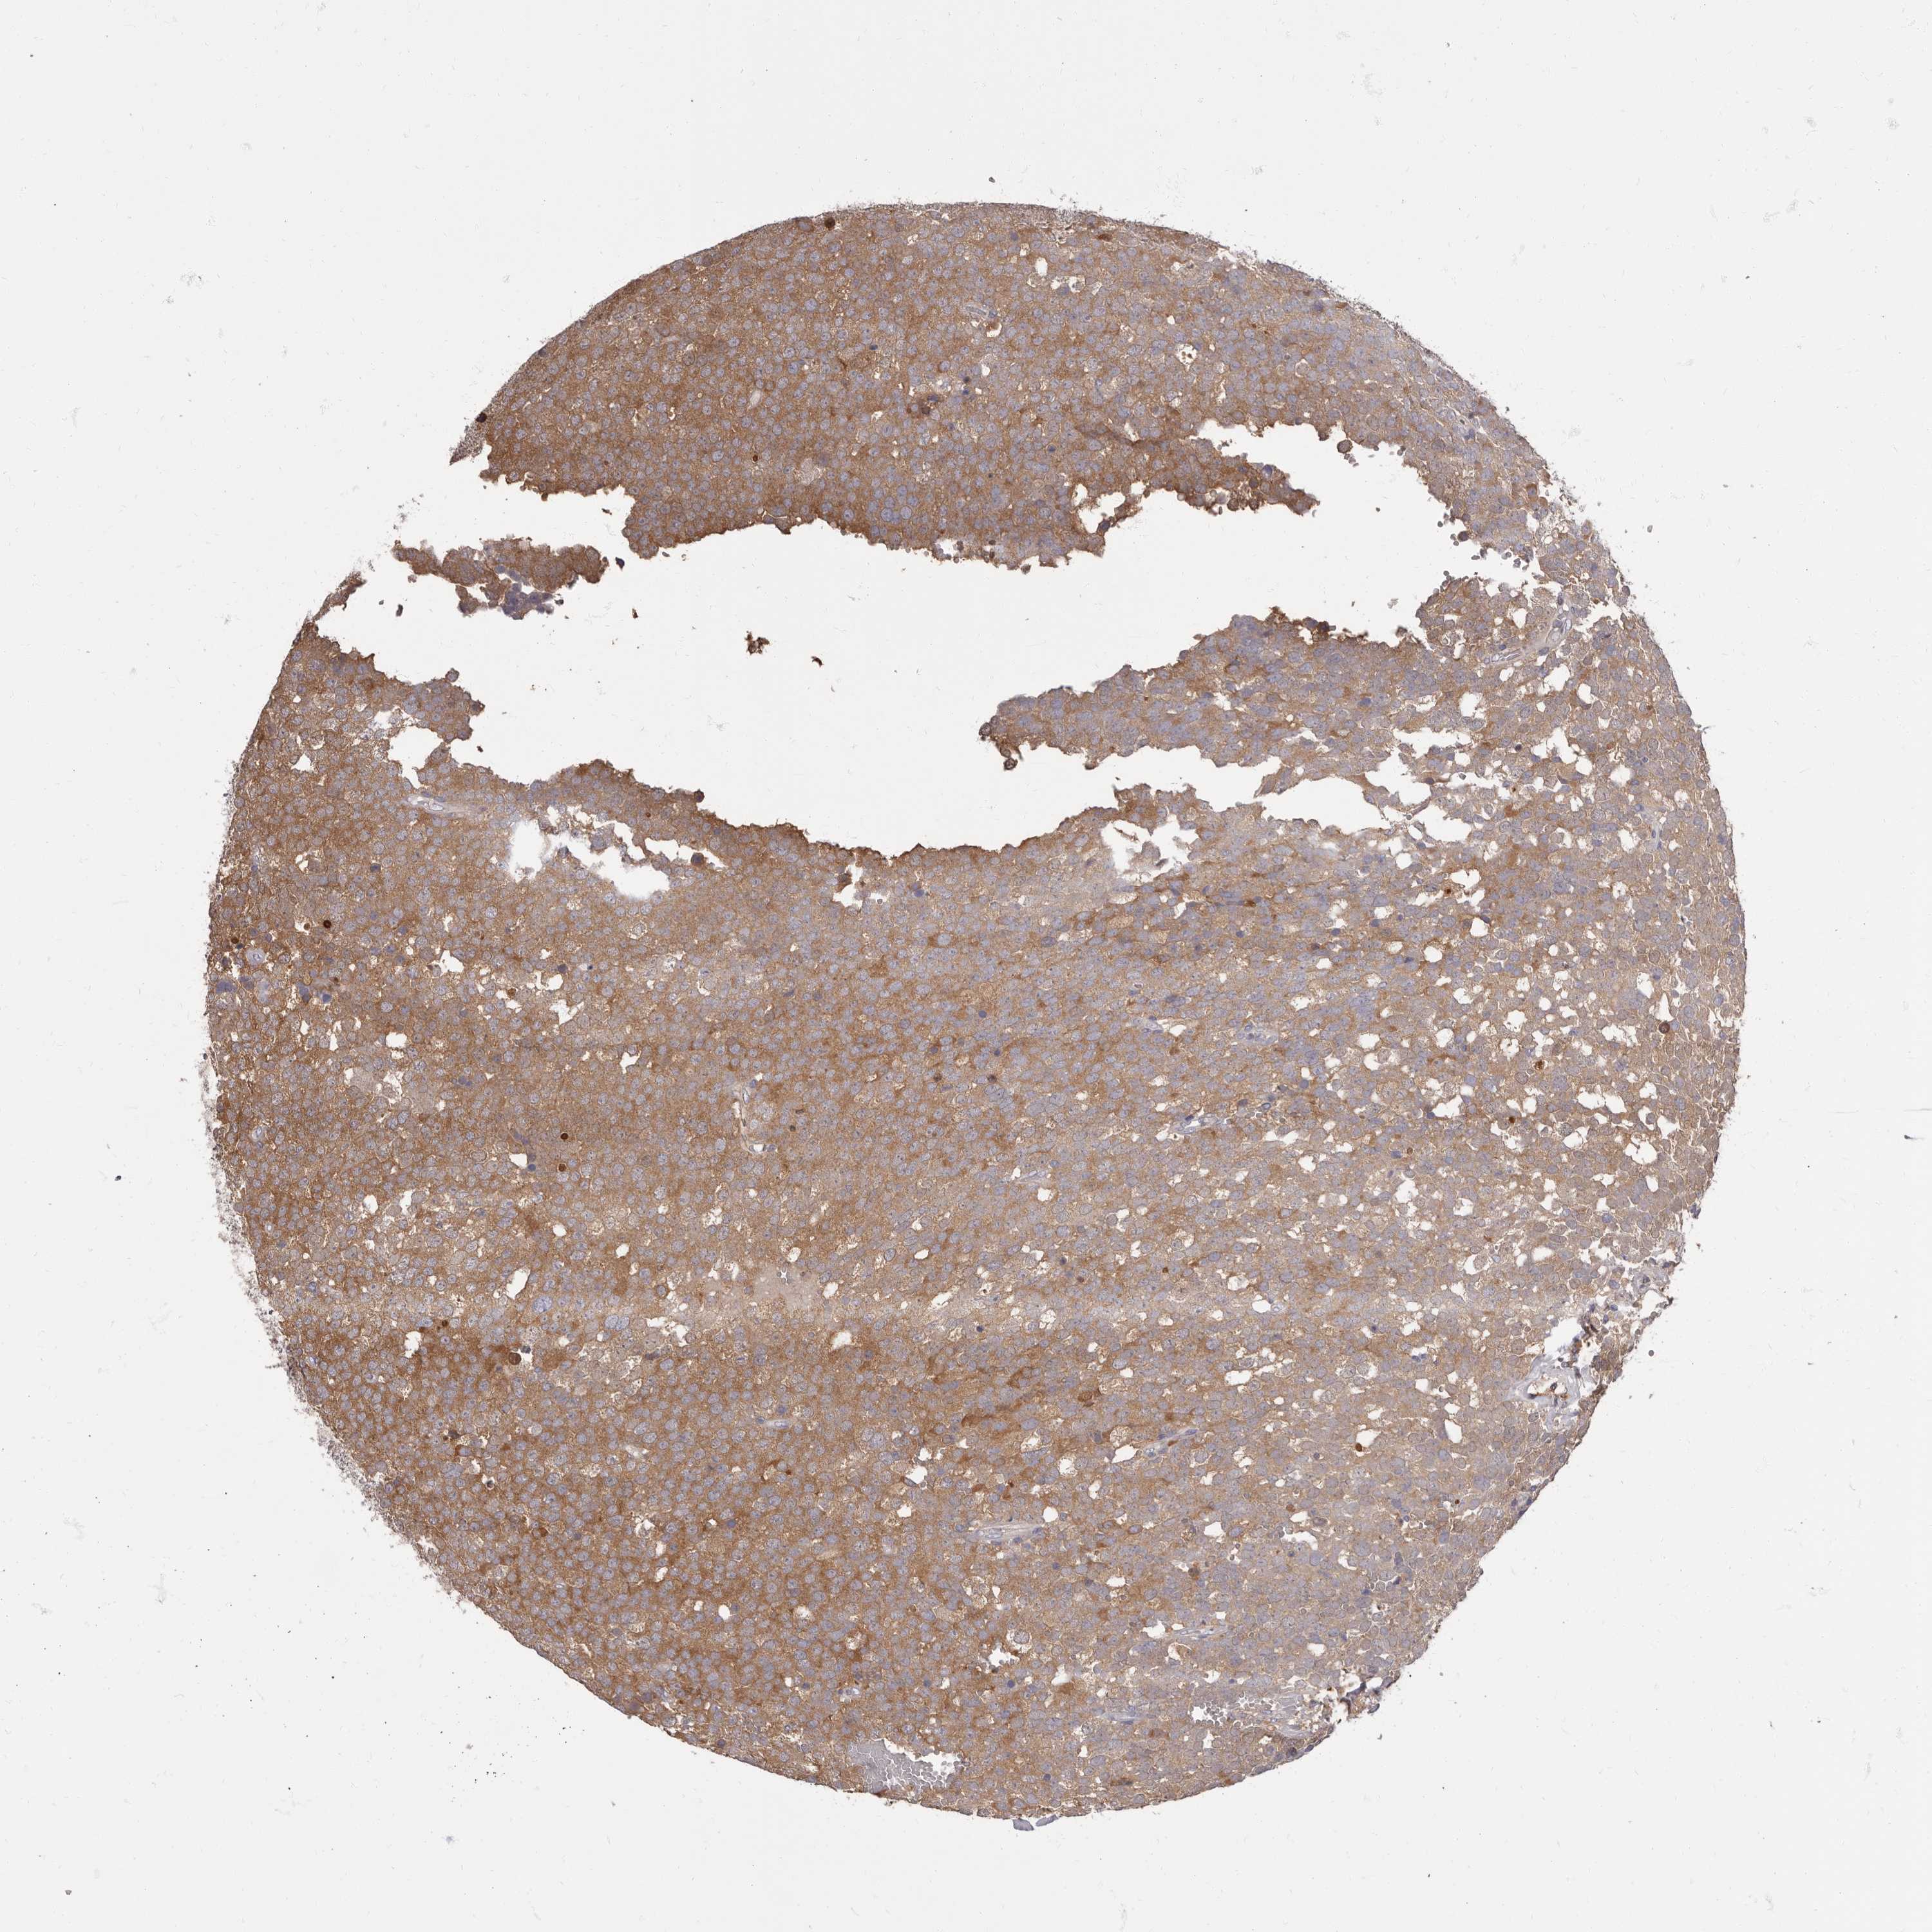

TESTIS CANCER - Protein expressioni

A mouse-over function shows sample information and annotation data. Click on an image to view it in a full screen mode. Samples can be filtered based on level of antibody staining by selecting one or several of the following categories: high, medium, low and not detected. The assay and annotation is described here.

Note that samples used for immunohistochemistry by the Human Protein Atlas do not correspond to samples in the TCGA dataset.

Antibody stainingi

Antibody staining in the annotated cell types in the current human tissue is reported as not detected, low, medium, or high, based on conventional immunohistochemistry profiling in selected tissues. This score is based on the combination of the staining intensity and fraction of stained cells.

Each image is clickable and will lead to virtual microscopy that enables deeper exploration of all samples and also displays staining intensity scores, fraction scores and subcellular localization as well as patient and tissue information for each sample.

Antibody HPA029700

Antibody HPA029701

Antibody HPA029702

Antibody HPA029703

Carcinoma, Embryonal, NOS

Seminoma, NOS